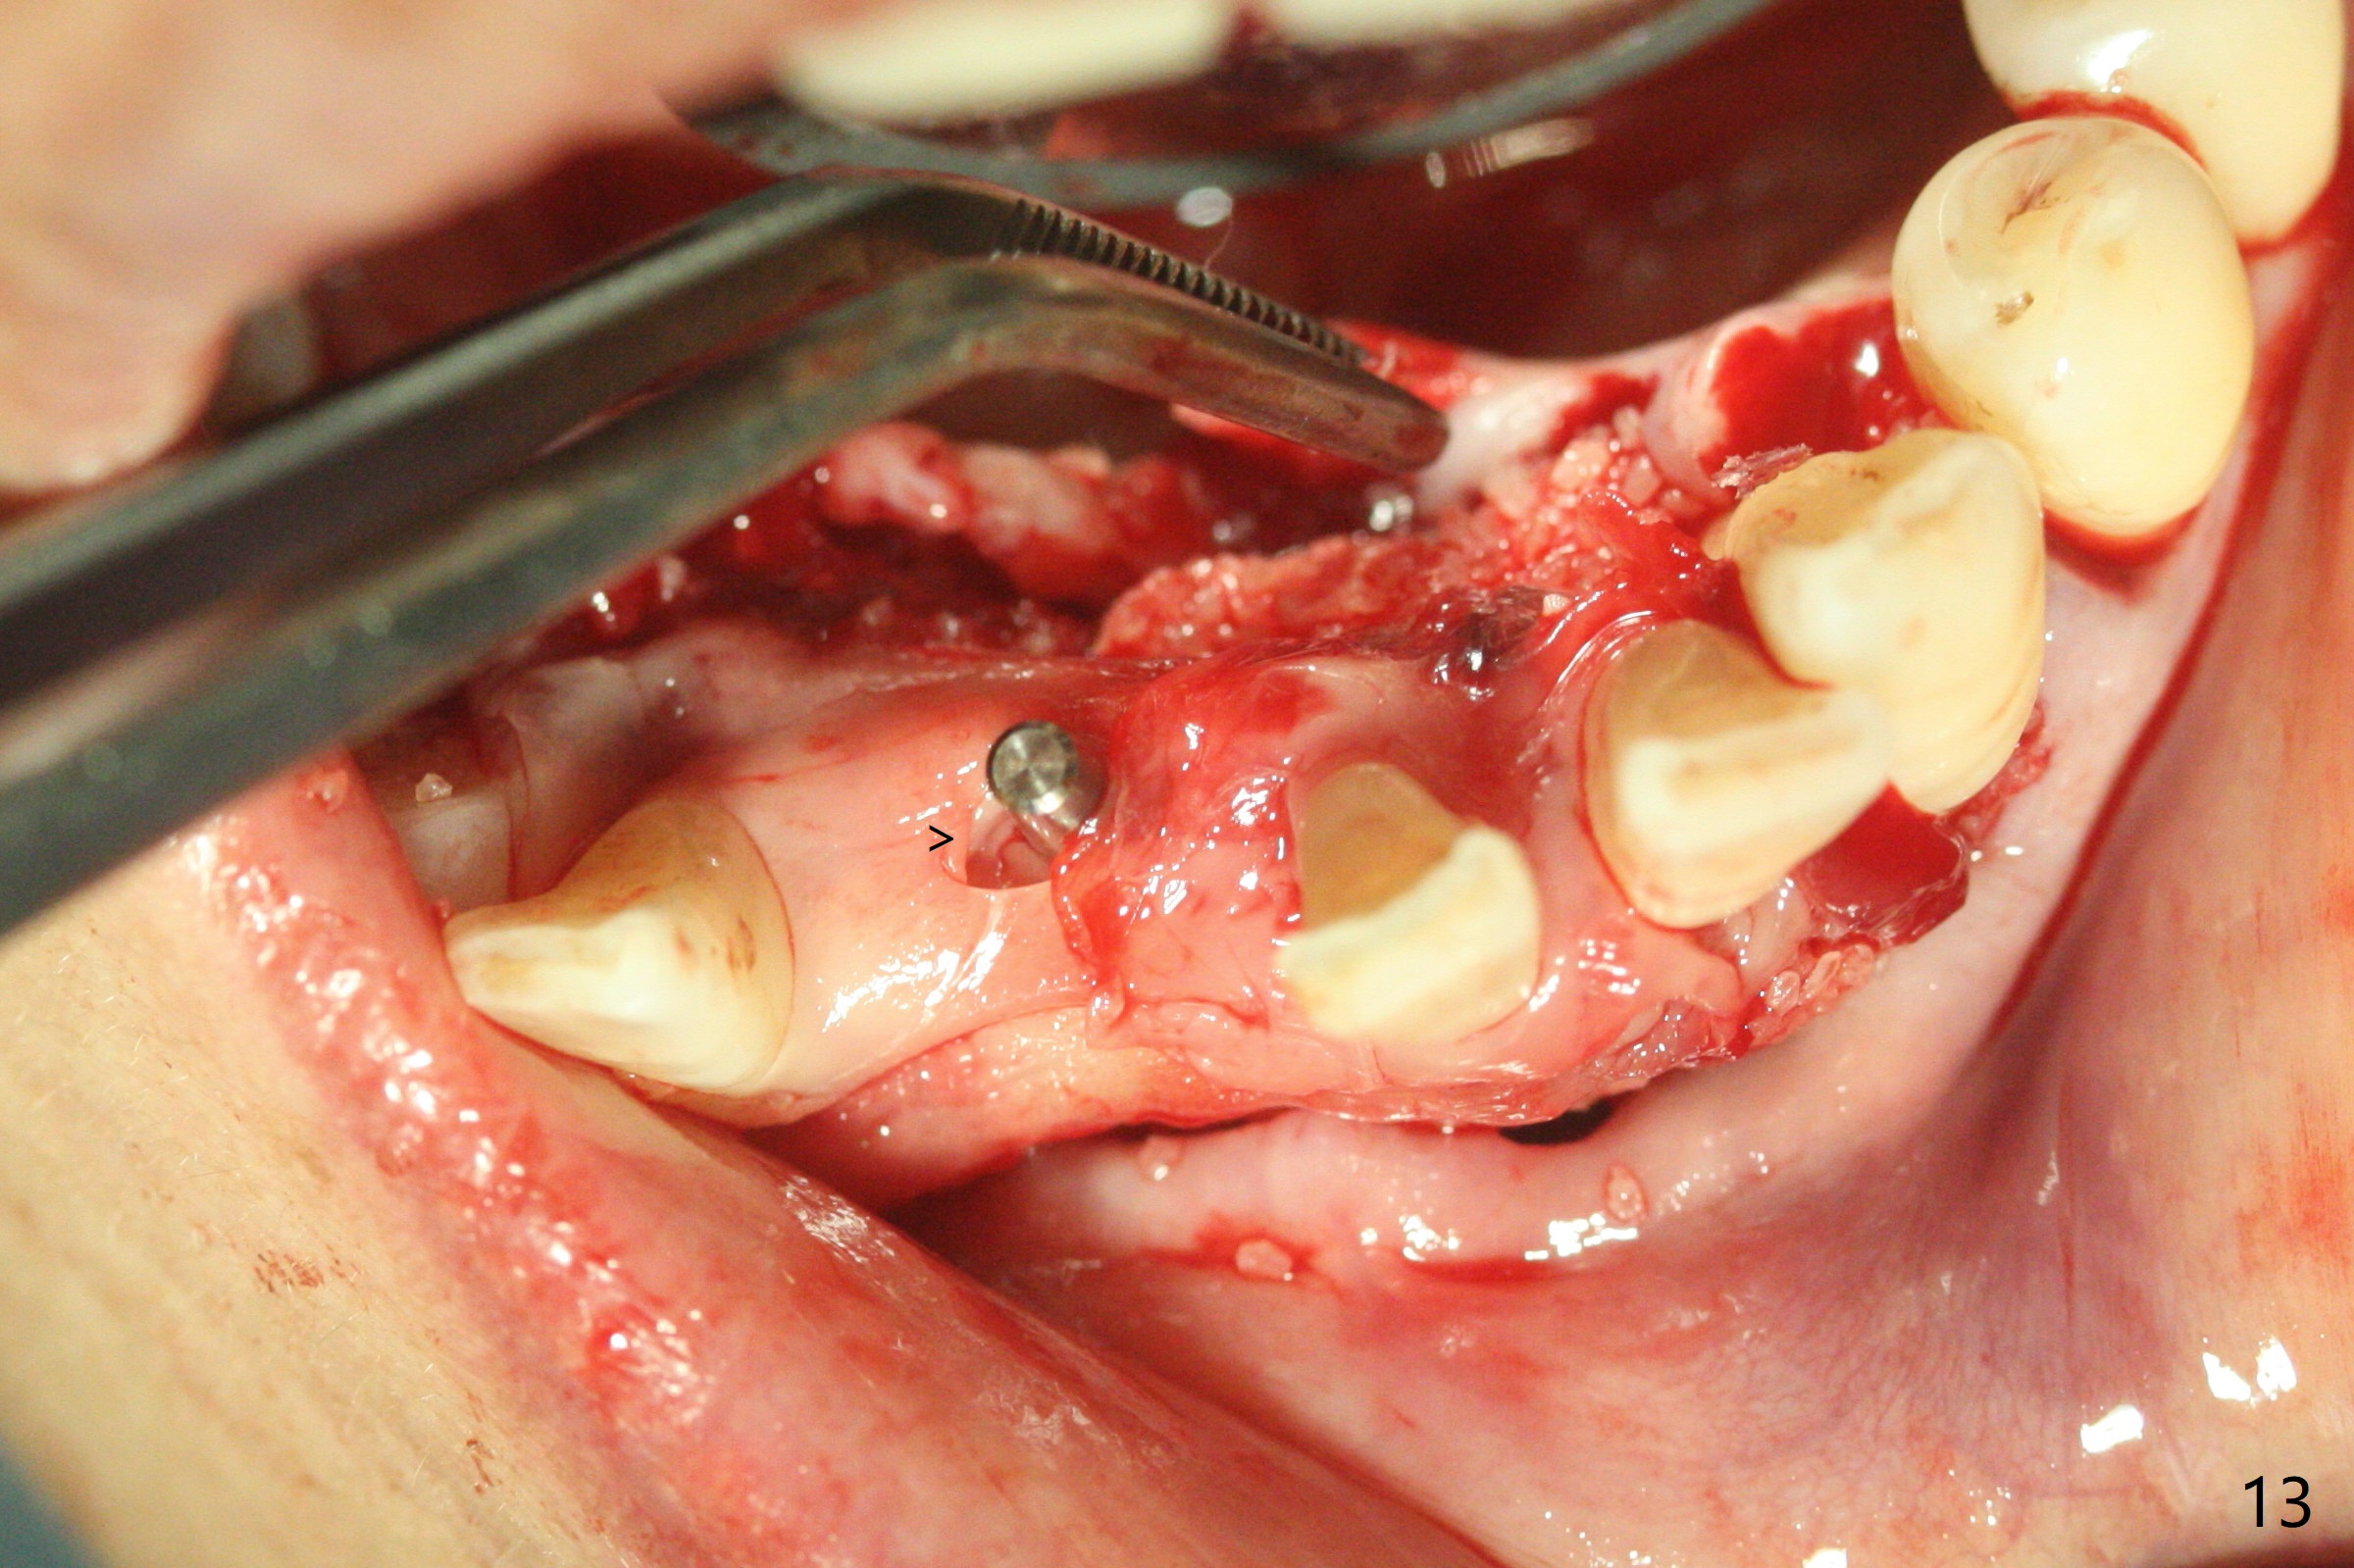

56岁女十分恐惧治疗,缺失右下1,其余切牙由于骨质吸收颊侧移位(图一:1,2),但是她不愿意拔除,同意右下1种植,牙周骨手术,植骨;植体整合后作为支抗,矫正移位下门牙。为了防止忘记舌侧瓣分离,先做舌侧切口(图二),然后颊侧瓣松弛分离(图三),包括使用前牙隧道刀(图四)切断颊侧骨膜,松弛到颊侧瓣能向舌侧牵拉3-4毫米(图五),舌侧瓣骨膜下广泛,深部分离(好像不能切断骨膜,图六),放置导板,磨平狭窄的牙槽嵴(图七:O(osteotomy)),植入2.5x12(4)毫米一段式植体(图八:故意舌侧植入,以便以后矫正),在颊侧骨板打多个出血洞(图八:箭头),然后把在平的器皿上形成的粘性骨板(sticky bone,图九),放置于植体和移位切牙周围(图十),接着使用消毒过的橡皮障punch(图十一(纸头相当于PRF膜;事先给助手示范))在三个PRF膜(图十二)打洞,套在植体和门牙上(图十三: 箭头),防止膜(图十四)和骨块(图十五,十六:*)移位,最后还必须使用最原始方法牙周敷料保护伤口(图十七)。术后9天,舌侧牙周敷料脱落,伤口稍微裂开(图十八)。术后18天撤除敷料,伤口裂开处有新鲜肉芽组织生长(图十九(*:下面是填入的骨粉,将是增宽的牙槽嵴(如果你是乐观主义者)),二十)。病人十分感激我们帮助她度过难关。她的确有sleep apnea,否定tongue thrust。术后三个月植体周围没有明显骨质吸收(图二十一至二十三),左下1,2轻度反合(图二十四),植体周围软组织健康(图二十五),5-5安置矫正器(图二十六,二十七,12 niti)。一周后下切牙向舌侧移动(图二十八),左下1,2反合纠正(图二十九)。再一周变化不大(图三十),植牙圈有些松动,两周后将重做临时牙冠,槽往舌侧移动。结果病人提前回来,植牙槽舌侧移位。一周后右下2不适(图三十一),尝试近中牵引(图三十二)。